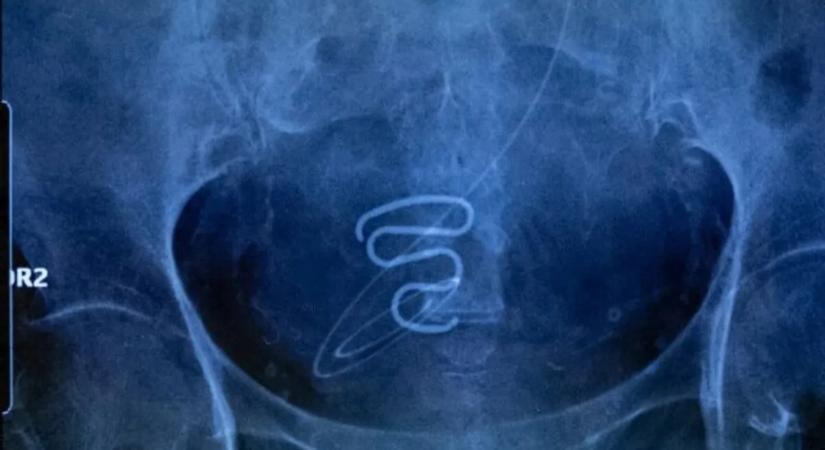

Több ezer inuit lányba és nőbe ültettek méhen belüli fogamzásgátlót a tudtuk és az engedélyük nélkül az 1960-as és 1970-es években.